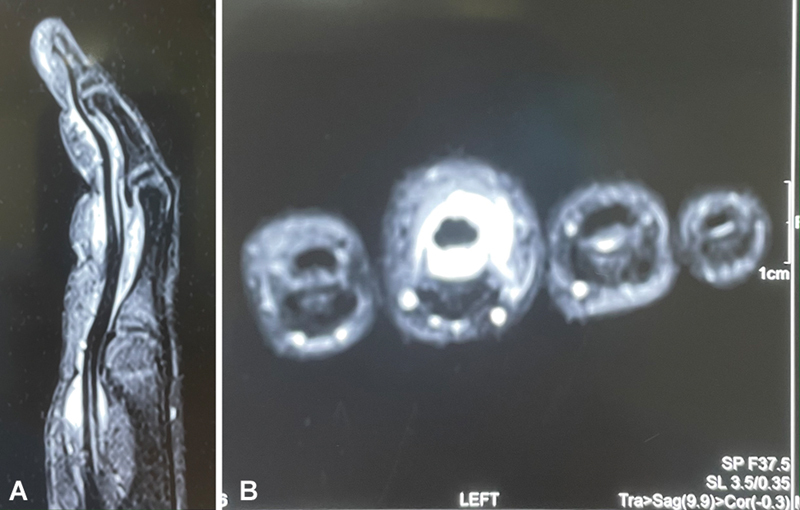

植物刺性滑膜炎是一种经常被忽视的损伤。我们报告一例5岁儿童左中指疑似刺伤的延迟病例,采用刺切除和完整屈肌滑膜切除术治疗,取得了良好的效果。正确的病史、临床检查和相关的放射学表现有助于诊断。由于持续肿胀和疼痛,患者可能寻求晚期治疗。可以给予抗生素;然而,在一个延迟的案例中,它的作用是有争议的。刺去除和完全腱鞘切除术提供了完全的恢复。

Plant thorn synovitis is a frequently missed and neglected injury. We report a delayed case of suspected thorn injury to the left middle finger in a 5-year-old child, which was treated with thorn removal and complete flexor synovectomy to achieve good results. Proper history, clinical examination, and correlated radiological findings can help in the diagnosis. Patients may seek late treatment due to persistent swelling and pain. Antibiotic may be given; however, in a delayed case, its role is debatable. Thorn removal and complete tenosynovectomy offers complete recovery.